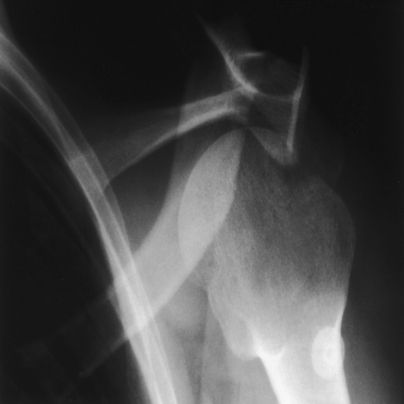

Structures shown: A lateral image of the shoulder and proximal humerus is projected through the thorax (Figs. 5-25 and 5-26).

The Lawrence1 method is used when trauma exists, and the arm cannot be rotated or abducted because of an injury. This projection shows the proximal humerus in a 90-degree projection from the AP projection and shows its relationship to the scapula and clavicle.

• Although this projection can be carried out with the patient in the upright or supine position, the upright position is much easier on a trauma patient. It also assists accurate adjustment of the shoulder.